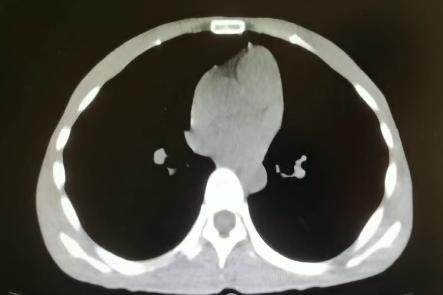

胸部CT:

右肺感染吸收,双侧胸腔积液吸收,双肺散在小结节,多系炎症,左膈抬高。

患者青年女性,慢性病程;主要表现为腹胀、呼吸困难,术后出现意识障碍、II型呼吸衰竭。经呼吸机辅助呼吸、对症支持等治疗后,患者意识恢复但呼吸困难无明显改善;既往有有粉尘接触史。查体见患者极度消瘦、营养不良,双肺呼吸音粗,可闻及散在湿啰音。血气示II型呼吸衰竭、高碳酸血症,轻度贫血,低蛋白血症,电解质紊乱,炎症指标、肌酶、BNP升高,院外腹水检查示漏出液,未见肿瘤细胞;胸部CT:双肺斑片影,抗感染治疗后病灶吸收;腹部增强CT:双侧附件区分别混杂密度团块影,内见多发囊泡影;心脏彩超:右心稍大,重度肺动脉高压。